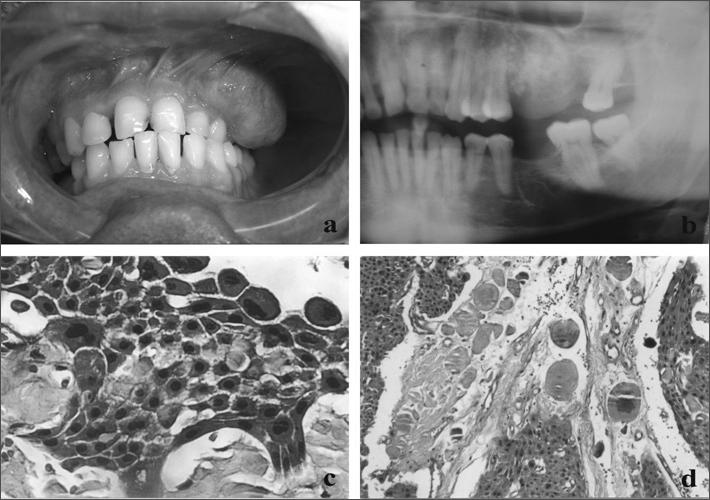

Calcifying epithelial odontogenic tumor of the maxilla.